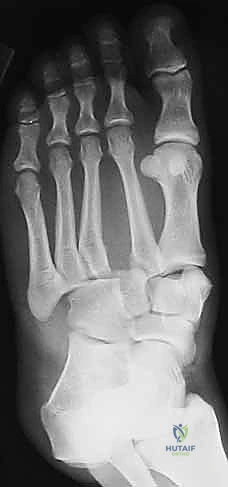

2. التصوير بالأشعة السينية (X-Rays) مع تحميل الوزن

الأشعة السينية العادية قد لا تظهر الإصابة إذا لم تكن العظام مزاحة بشكل كبير. السر يكمن في طلب أشعة سينية أثناء وقوف المريض وتحميل وزنه على القدم المصابة (Weight-bearing X-rays).

* يبحث الدكتور هطيف عن "علامة الفليك" (Fleck Sign)، وهي قطعة عظمية صغيرة مكسورة ومسحوبة من قاعدة المشط الثاني أو العظم المسماري الإنسي، وهي دليل قاطع على تمزق رباط ليزفرانك.

* كما يتم قياس المسافة بين قاعدة المشط الأول والمشط الثاني. أي اتساع يزيد عن 2 ملم يُعتبر غير طبيعي ويشير إلى عدم الاستقرار.